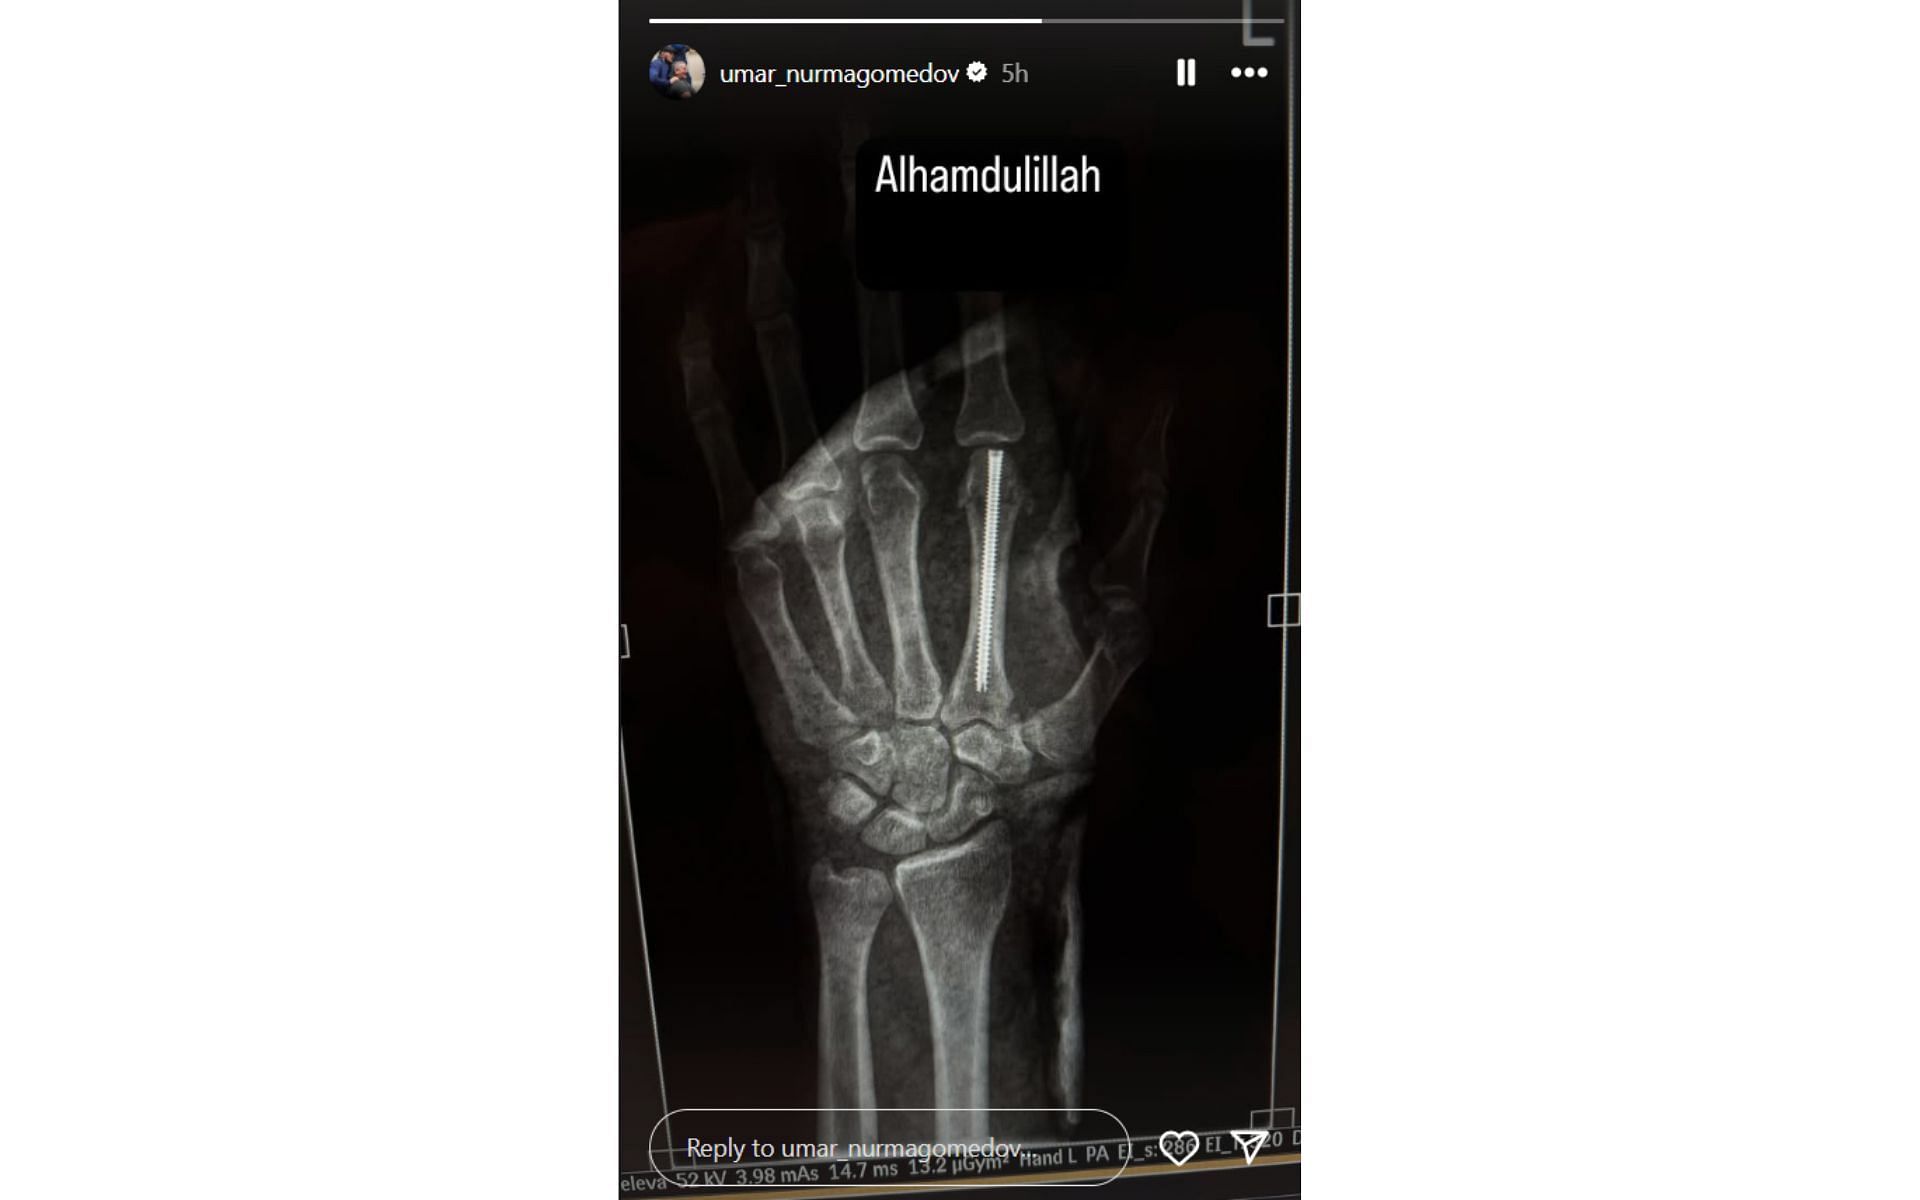

Nurmagomedov recently underwent surgery to fix the injury and shared an X-ray image of his hand on his Instagram story. The short caption to the post read:

"Alhamdulillah [Praise be to God]"

Based on the visual observation of the X-ray image, it appears that the Dagestani fighter fractured the first metacarpal in his left hand and got an intramedullary headless screw fixation. The technique enables the fixation of fractures without needing external prominent hardware.